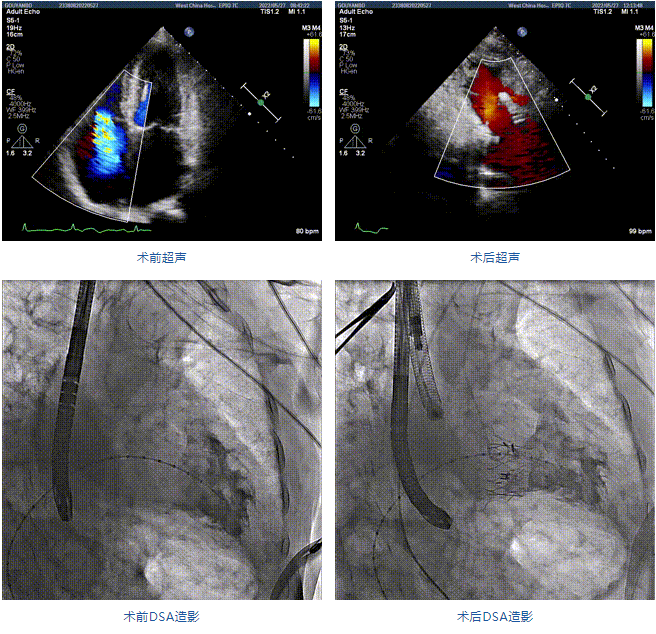

89歲男性。術(shù)前超聲報(bào)告顯示:雙房增大,左室壁肥厚,主、肺動脈增寬,三尖瓣重度反流。

團(tuán)隊(duì)前期經(jīng)過多次討論,制定了周密的手術(shù)策略和預(yù)案。由于患者已是近九旬的超高齡老人,傳統(tǒng)外科開胸手術(shù)風(fēng)險極高,純介入經(jīng)血管三尖瓣替換能夠明顯減少創(chuàng)傷。術(shù)中陳茂及馮沅教授結(jié)合體表定位在造影指示下精準(zhǔn)穿刺右側(cè)頸靜脈并預(yù)置兩把血管縫合器。成功建立經(jīng)皮血管入路后在食道超聲和DSA的引導(dǎo)下順利完成人工瓣膜植入,術(shù)后超聲和造影顯示人工三尖瓣同軸性良好,瓣架固定牢靠,無反流和瓣周漏,平均跨瓣壓差降為1mmHg。術(shù)畢收緊預(yù)置的血管縫合器縫線完成止血,縫合效果滿意,在手術(shù)室即刻拔除氣管插管。